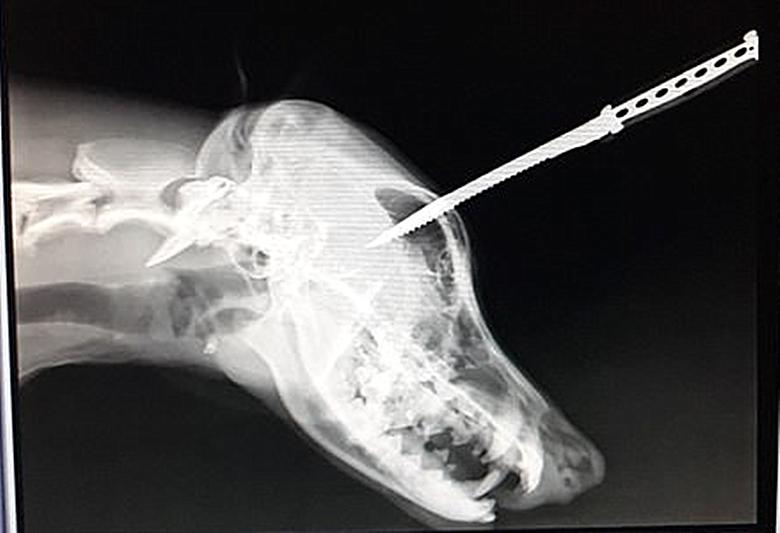

这是一只叫Duke的德牧

几天前和主人出去散步

突然冲出一个想要抢劫的强盗

危急时刻

狗狗不顾一切冲出去和歹徒对抗

歹徒见状

用手里锋利的牛肉刀直接插到

狗狗的头上

(被送医时的Duke)

尽管头上中刀,满脸鲜血

但它依然坚持着冲着歹徒吠叫

最终吓跑了歹徒

它却瘫痪般地倒在了地上

主人发现狗狗还有一丝呼吸后

迅速把它带到了当地的医院

X光显示刀插入头部8厘米

再有几毫米,狗狗就救不回来了